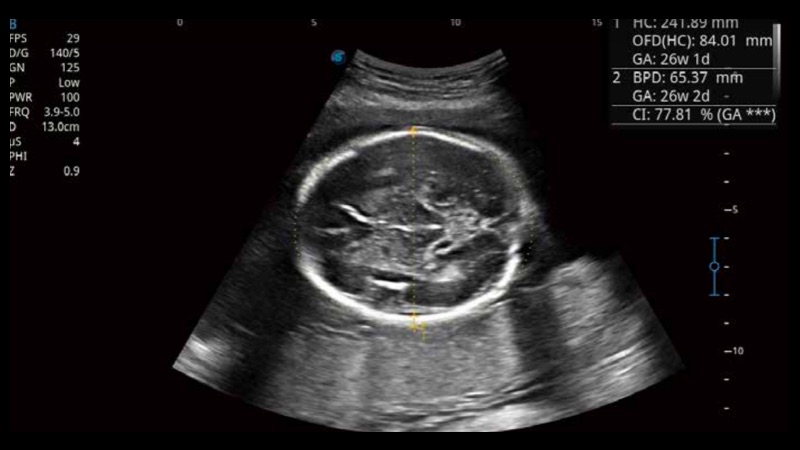

S-Fetus基于大數(shù)據(jù)深度學(xué)習(xí)算法,能夠幫助您在產(chǎn)前篩查過程中智能識(shí)別胎兒標(biāo)準(zhǔn)切面、自動(dòng)測(cè)量并錄入報(bào)告。一個(gè)按鍵,即可智能、精準(zhǔn)、高效地獲取胎兒生理指標(biāo),極大簡化您的產(chǎn)科檢查操作。

可快速對(duì)產(chǎn)科掃查切面完成胎兒生理學(xué)參數(shù)的自動(dòng)測(cè)量,減少操作者按鍵次數(shù),大幅提升檢查效率。